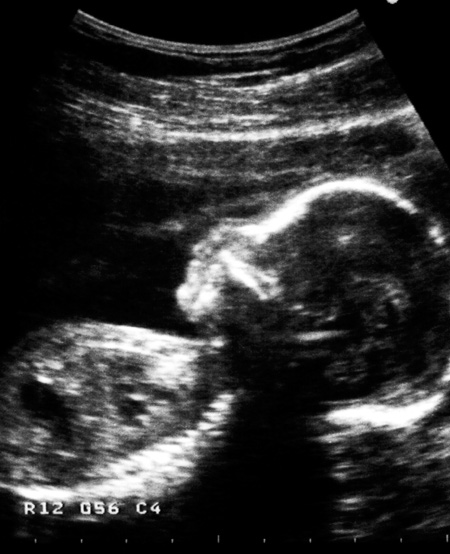

Illustrasjonsfoto: Elisabeth Edén/Bildhuset/TT